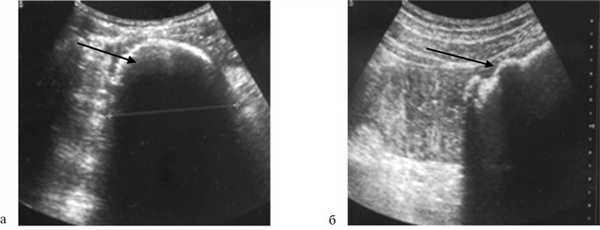

При УЗИ органов брюшной полости у 6 (35,3%) больных, поступивших в сроки до 24 ч от начала заболевания, патологических изменений в тонкой кишке не было выявлено, в то время как при сроках более 24 ч у 11 (64,7%) пациентов отмечались расширенные петли тонкой кишки (более 4 см в диаметре) с маятникообразным продвижением содержимого. Причину непроходимости у 2 (11,8%) пациентов удалось выявить при УЗИ, а именно гиперэхогенные образования (фитобезоары) (рис. 1).

Рис. 1. Ультразвуковое исследование органов брюшной полости (а и б). Стрелкой указана причина непроходимости ― фитобезоары. Чувствительность метода составила 70%.